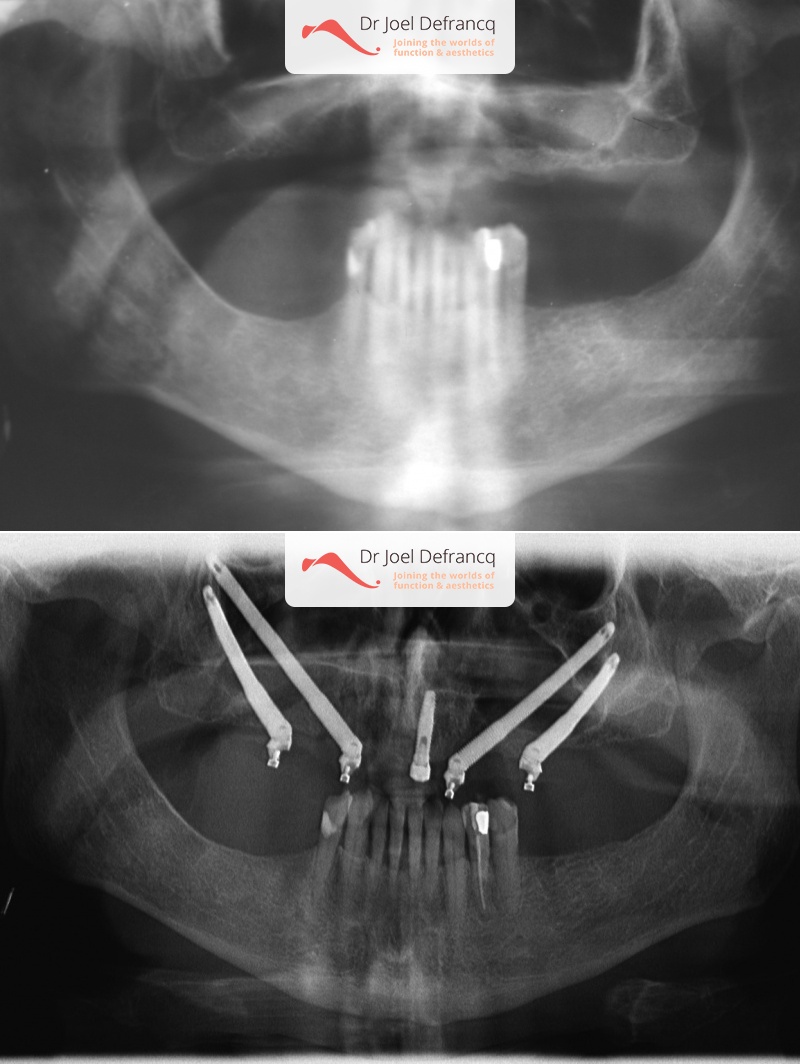

Maurice

Diagnose van het gezicht

- Gekanteld beetvlak

Behandeling tandheelkundige implantaten

- Zygoma implantaten